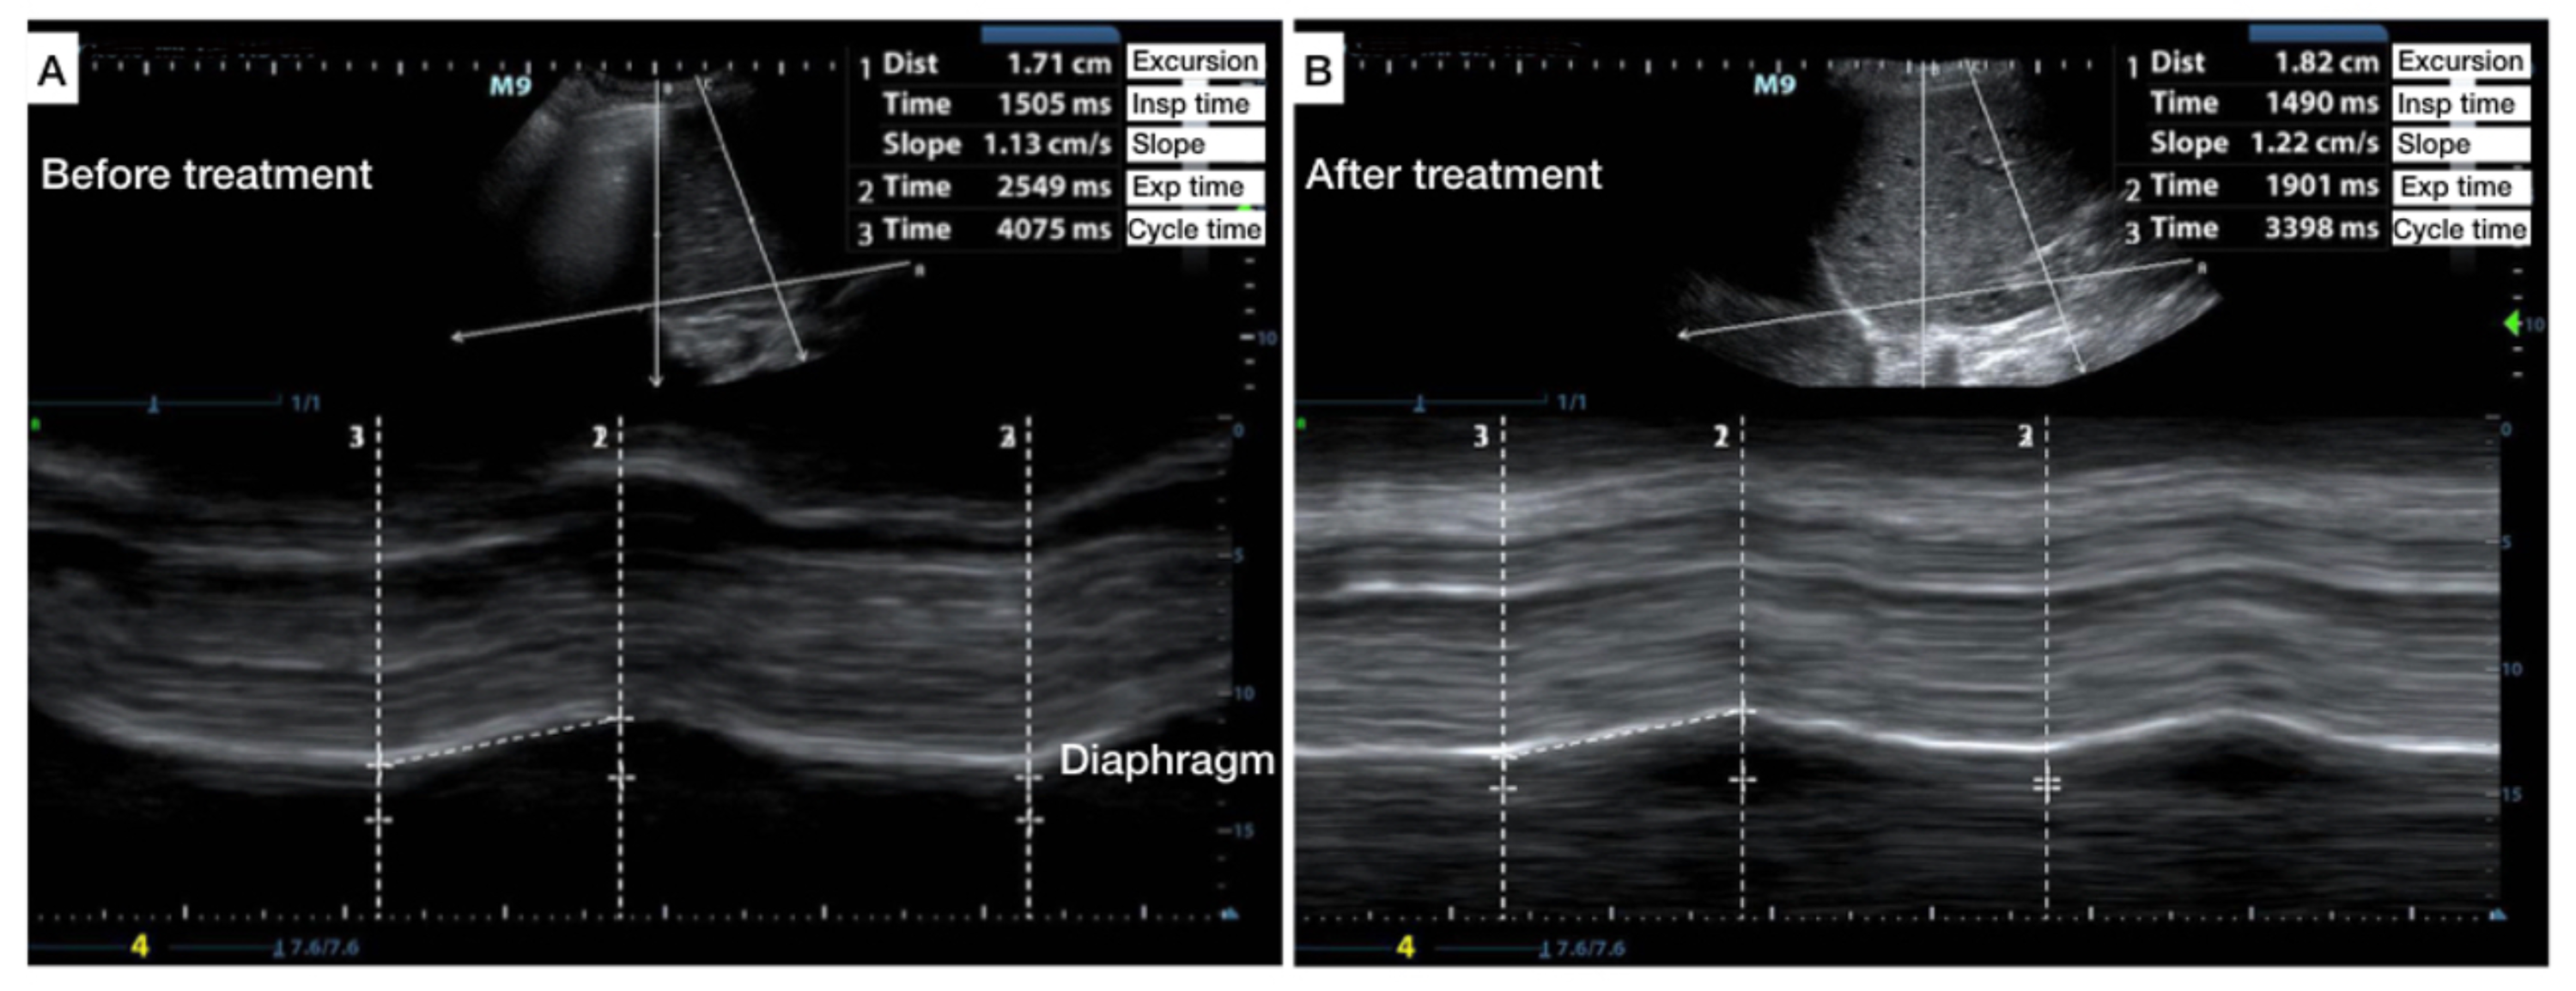

Diaphragm excursion and respiratory functions before and after thoracic Diaphragmatic Excursion Test We found an outstanding value for. This article describes the different methods used to measure diaphragmatic. The fluoroscopic sniff test is a useful addition to diaphragm fluoroscopy and is used to evaluate diaphragmatic contraction and excursion in patients with suspected. Diaphragmatic excursion is the movement of the thoracic diaphragm during breathing. Check us out on facebook for daily free review. Diaphragmatic Excursion Test.

Variation in diaphragmatic excursion during a sniff test before and Diaphragmatic Excursion Test We found an outstanding value for. The fluoroscopic sniff test is a useful addition to diaphragm fluoroscopy and is used to evaluate diaphragmatic contraction and excursion in patients with suspected. Check us out on facebook for daily free review questions and updates!. This article describes the different methods used to measure diaphragmatic. Diaphragmatic excursion is a quantitative measure of expiratory. Diaphragmatic Excursion Test.